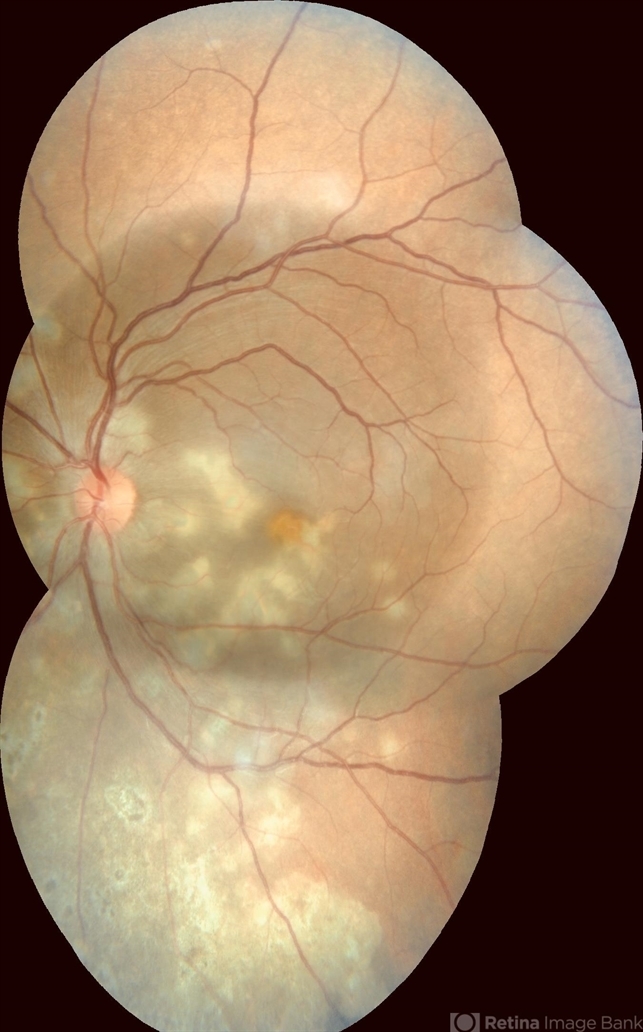

They appear to be at different stages of healing though, with the peripheral inferior ones, appear inactive, older & atrophic.

I am sure the darker, perfect circle in the middle, is just an artifact due to different exposure and not an exudative RD, as it is too perfectly round (corresponding with central color photo frame, with the active choroidal lesions mostly below.

Could this be Serpiginous Choroiditis ??

- choroiditis, disseminated choroiditis

- A 25-year-old male patient presented with defective vision noticed since last 2 weeks. No significant past history. Anterior segment was normal. Vision RE 6/6, LE 6/60. Other eye was normal on examination.